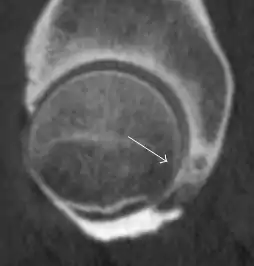

Synovial chondromatosis can be confidently diagnosed by X-ray when calcified cartilaginous chondromas are seen. However, other synovial proliferative processes, such as pigmented villonodular synovitis, require MRI for accurate diagnosis, although noncalcified synovitis can be suspected in radiographs by indirect signs, such as soft tissue swelling and/or erosions in the femoral head, femoral neck, or acetabulum (Figure 7).[1]

Figure 7:

Axial CT image of pigmented villonodular synovitis eroding the posterior cortex of the femoral neck.[1]

In synovial proliferative disorders, MRI demonstrates synovial hypertrophy. In the case of PVNS, characteristic foci of low signal intensity related to hemosiderin deposition are better seen on gradient echo T2* images (Figure 7). In the case of synovial osteochondromatosis, the synovial hypertrophy is accompanied by intermediate signal cartilaginous loose bodies and/or low signal calcified loose bodies.[1]